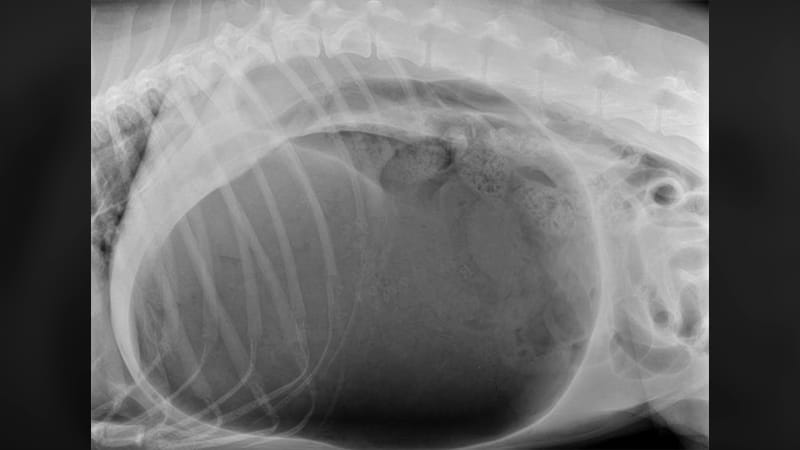

Confirming the Diagnosis

Radiographs (X-rays) are the gold standard for confirming GDV. The classic “double bubble” appearance distinguishes true volvulus from simple gastric dilatation, allowing our team to proceed with appropriate treatment.